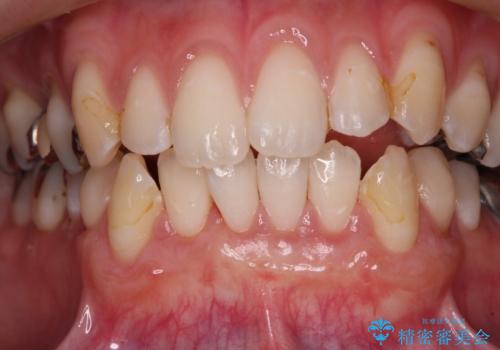

- 歯肉退縮による知覚過敏を気にして来院された患者様です。

診察したところ、知覚過敏をむし歯と勘違いし、一生懸命磨いたことで横縞模様ができるほどでした。

歯肉退縮に対して、上顎からの結合組織移植術(CTG)により、歯根の被覆を行うとともに、歯肉の厚みを増すことで将来の退縮リスクを抑制することとしました。